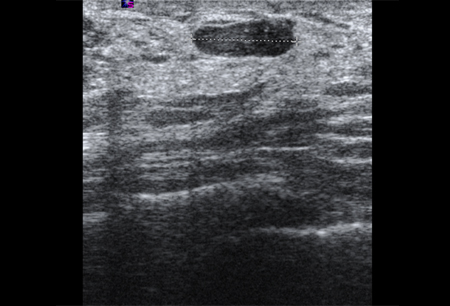

Ultrasonographic image of a fibroadenoma

Courtesy of Dr Lane Roland, University of Louisville; used with permission